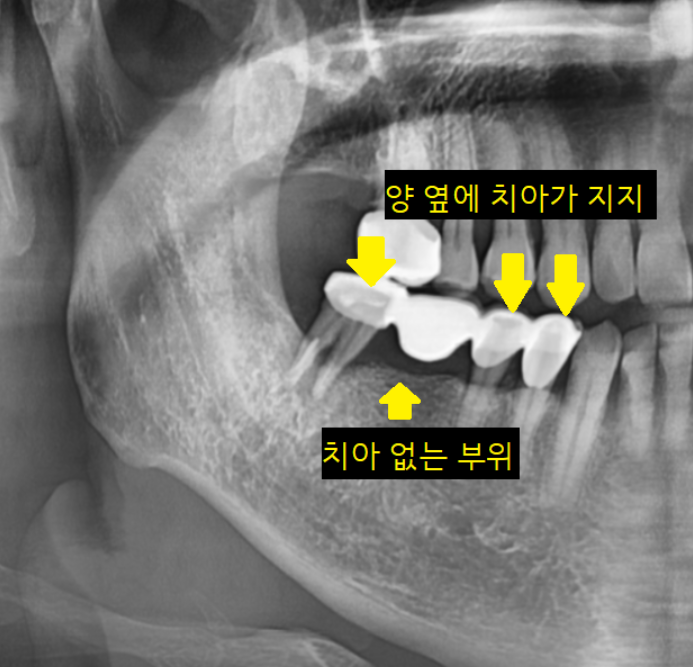

위에 사진속 환자분처럼

치아가 상실된 개수가 1개도 없지만

임플란트는 묶어서 제작해드렸습니다.

임플란트는 각각 심었는데 말이죠~?

왜 머리를 붙여서 만드느냐!!